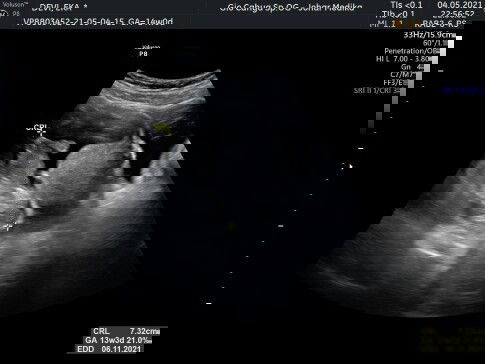

Bund saya mau tanya. Masa kehamilan saya 13W3D cara baca hasil USGnya itu gimana nggeh Bund? Terus dokter bilang itu ekor bukan kaki maksudnya gimana Bund? Saya bingung. Kalau bunda bunda ada yang tau dan boleh ngasih hasil USG 13W3D ke saya. Boleh saya minta penjelasannya bund#seriusnanya